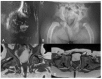

Mucolipidosis type II (MLII) is a rare lysosomal storage disorder caused by defective trafficking of lysosomal enzymes. Severe skeletal manifestations are a hallmark of the disease including hip dysplasia. This study aims to describe hip morphology and the natural course of hip pathologies in MLII by systematic evaluation of plain radiographs, ultrasounds and magnetic resonance imaging (MRI). An international two-centered study was performed by retrospective chart review. All MLII patients with at least one pelvic radiograph were included. A total of 16 patients were followed over a mean of 3.5 years (range 0.2-10.7 years). Typical age-dependent radiographic signs identified were femoral cloaking (7/16), rickets/hyperparathyroidism-like changes (6/16) and constrictions of the supra-acetabular part of the os ilium (16/16) and the femoral neck (7/16). The course of acetabular and migration indexes (AI, MI) significantly increased in female patients. However, in the overall group, there was no relevant progression of acetabular dysplasia with a mean AI of 23.0 (range 5°-41°) and 23.7° (range 5°-40°) at the first and last assessments, respectively. Better knowledge on hip morphology in MLII could lead to earlier diagnosis, improved clinical management and enables assessment of effects of upcoming therapies on the skeletal system.